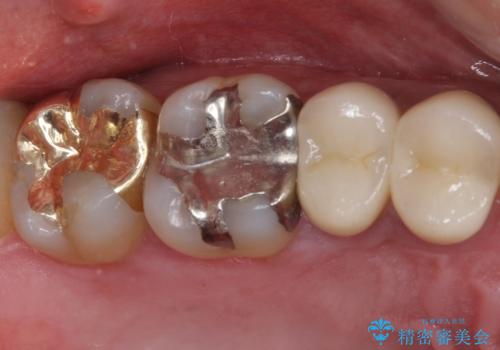

ゴールドインレーは銀歯のインレーやセラミックインレーと比べ、「技工操作の精度が高く、適合が著しく良い」というメリットがあります。特に上の奥歯は歯科医師の操作が行いにくいため、「適合の良さ」は再治療のリスクを防ぐ上でとても重要な要素となります。

上の奥歯は金属色が見えることもないため、審美的な問題は全くありません。

咬み心地はとても良好で、全く違和感がなく、患者様には大変満足していただきました。